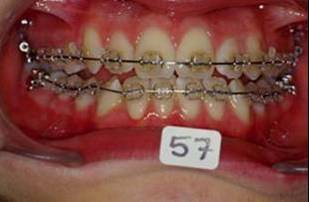

En fouillant dans mes cas j'ai trouve celui ci qui presente une beance assez importante. Je me suis rappele qu'un certain message etait lance il y a qq temps a propos d'un enfant qui presente une beance et de savoire comment faire dans ce cas. Je pense qu'il est interessant de voir comment les uns et les autres prennent en charge ce type de cas. Il s'agit d'un fille de 12 ans, succion de pouce, interposition linguale totale, beance de molaire a molaire, respiration mixte, incompetence labiale au repos, fonction labiale serree. Le total quoi!!! Voici la premiere serie de photos

4- Collage de l'arcade sup, presque 6 mois apres et voici le photo apres seance de college

Collage bas fait presque 3 mois apres le haut, avec des elastiques verticaux pendant 3 semaines seulement. Et voici les photos, la suite je vous en passe car il s'agit de simple finition.

P.S. photos au moment du collage bas